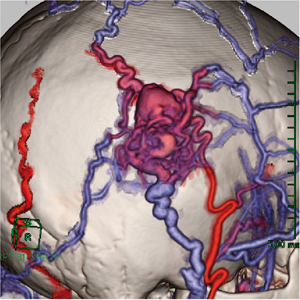

一般的に,AVMの血液循環は急速であるため,動脈優位相で流出血管の描出が予想できる。そのため,静脈優位相を撮影することによって,動脈優位相の流出血管の同定が可能であると考えられた。単純・動静脈優位相の3相をVirtualPlaceに転送し,サブトラクション機能にて動脈優位相から単純を差分して流入動脈,nidus,一部の流出静脈の三次元画像を取得することができる。また同様に,静脈優位相から単純を差分することによって,流出静脈相の画像が取得できる(図1)。そして,動脈優位相と静脈優位相の血管を色分けして表示し,マルチボリューム機能により,色の重なりの強い部分と弱い部分から動脈と静脈を判断する。そのおのおのの三次元画像から,余分な血管を削除していくことによって,最終的にnidusを取り巻く流入・流出血管を描出した(図2)。

図1 症例1:右側頭部AVM

a:動脈優位相−単純の差分画像 b:静脈優位相−単純の差分画像。

色分けしておくことによって時相を判別できる。